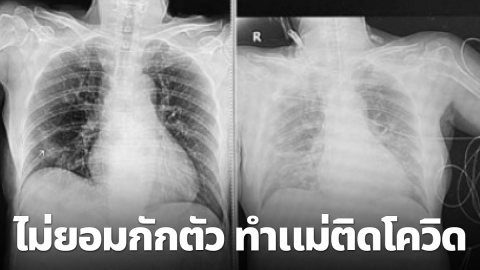

สุดช็อก ลูกสาวกลับจากเมืองนอก ไม่กักตัว ทำแม่ติดเชื้อ อาการหนัก ระบบหายใจล้มเหลว